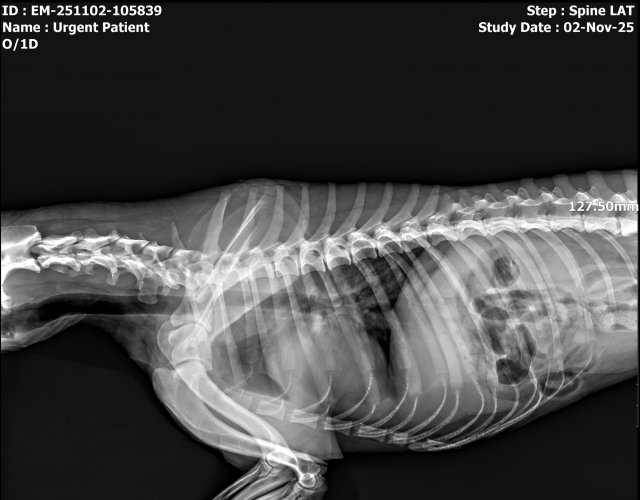

Caine accidentat

O doamna a gasit un caine lovit de masina si l-a tras pe marginea drumului pentru a suna peste tot in cautare de ajutor. Am raspuns pozitiv si am facut totul pentru el. Din pacate nu a putut fi salvat, decedand a doua zi dupa interventia chirurgicala. Foarte probabil din cauza unei embolii pulmonare. Le multumim celor care au donat. Medicul a anulat factura iar banii vor ajuta desigur alte animale de care ne ocupam zilnic.